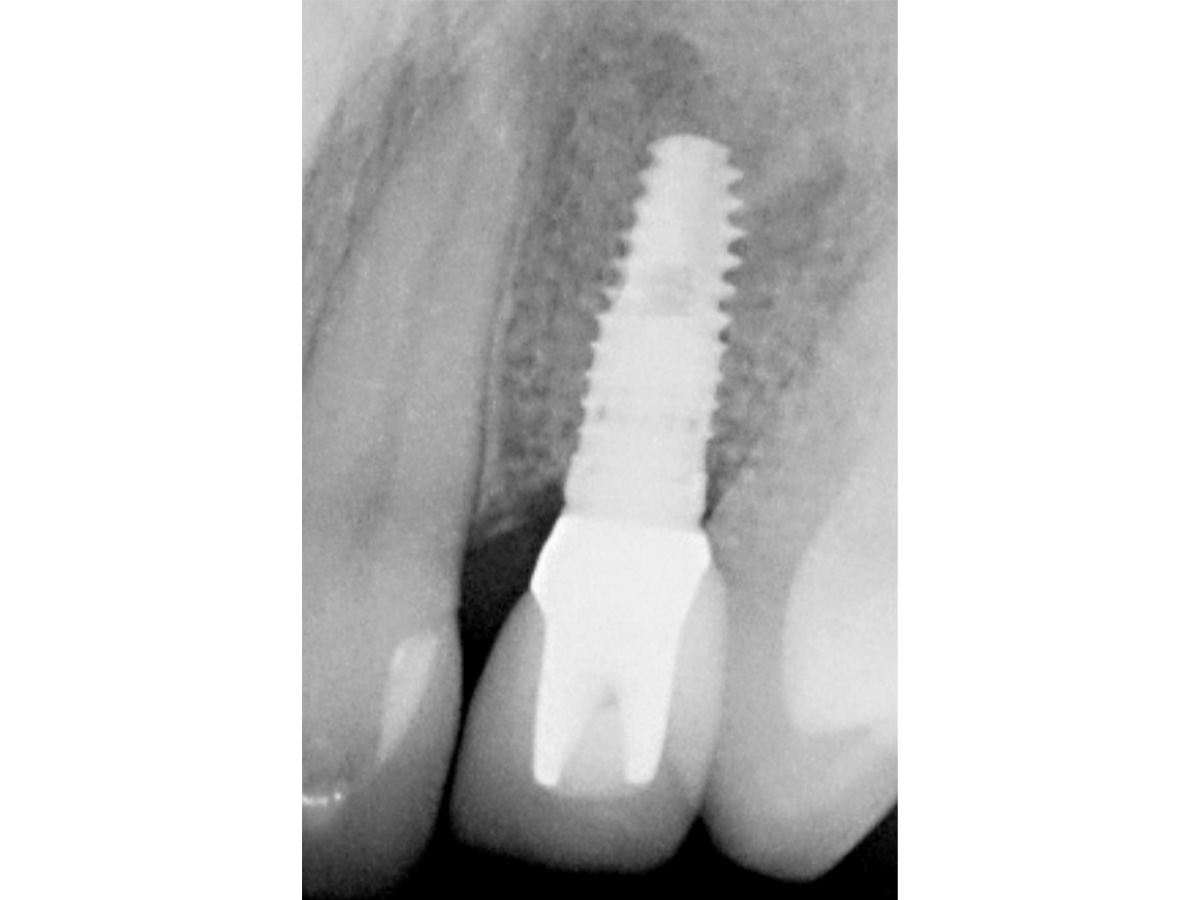

Abbildung 12

Regenerierter Alveolarkamm vor der prothetischen Versorgung.

Abbildung 13

6 Monate nach vollkeramischer Versorgung.

Zu diesem Zeitpunkt kann klinisch und röntgenologisch ein deutlicher Zugewinn von Volumen verzeichnet werden, so dass ein Implantat vom Durchmesser 3,8 mm in der korrekten dreidimensionalen Position eingesetzt werden kann. Mit den beschriebenen augmentativen Maßnahmen konnte ein ästhetisch ansprechendes Gesamtergebnis realisiert werden.